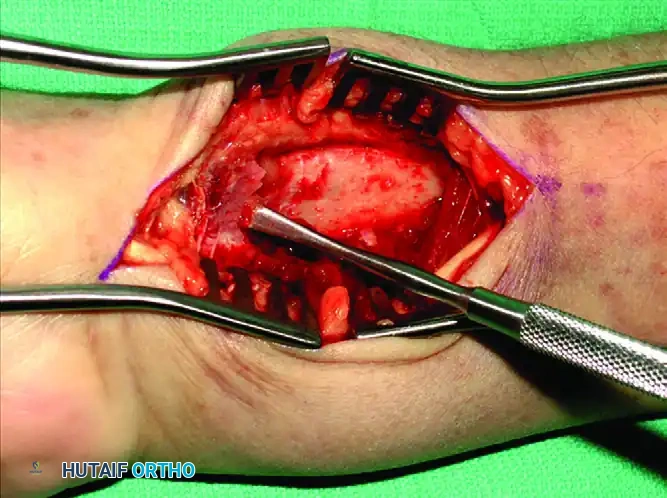

Deep Dissection: The floor of the FCR sheath is incised to access the deep compartment. The flexor pollicis longus (FPL) muscle belly is identified and partially detached or retracted ulnarly from the radius to expose the underlying pronator quadratus.

Pronator Quadratus Elevation: Using a Freer elevator or electrocautery, the pronator quadratus is elevated from its radial insertion in an L-shaped fashion, reflecting it ulnarly.

Fracture Exposure and Reduction: The fracture line is now fully exposed. Hematoma is evacuated, and the fracture is reduced under direct vision and fluoroscopic guidance.

Associated Surgical & Radiographic Imaging